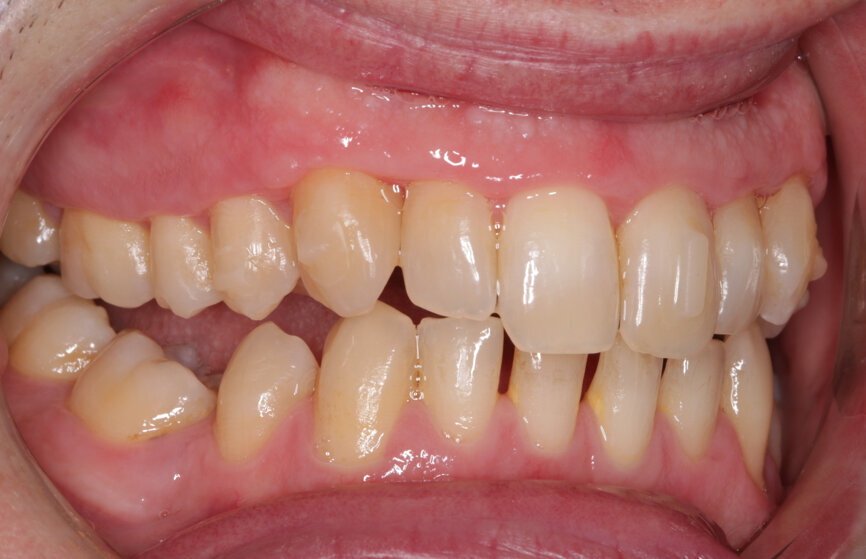

Fig. 3: Pre treatment left lateral

Fig. 4: Pre-treatment right lateral

My examination revealed nothing abnormal with his extra- or intra-oral soft tissue, temporomandibular joint or range of motion. However, his oral hygiene was poor, which was not helped by the crowding of his maxillary anterior segment. In addition, tooth #48 was carious. I carried out a full orthodontic assessment (Table 1) and took photographs.

I explained that the maxillary teeth could and should be aligned, as this would likely result in easier cleaning of the teeth, plus it would improve the appearance. The patient and I agreed that the mandibular teeth could remain untouched, as this would keep the cost down, but mainly because they did not bother him. The priority was to stabilise his periodontal condition. A basic periodontal examination Code 3 and heavy bleeding were recorded in each sextant. At that visit, I performed a gross scaling using the ultrasonic scaler and used a model to demonstrate both the use of flossettes and an oscillating toothbrush.